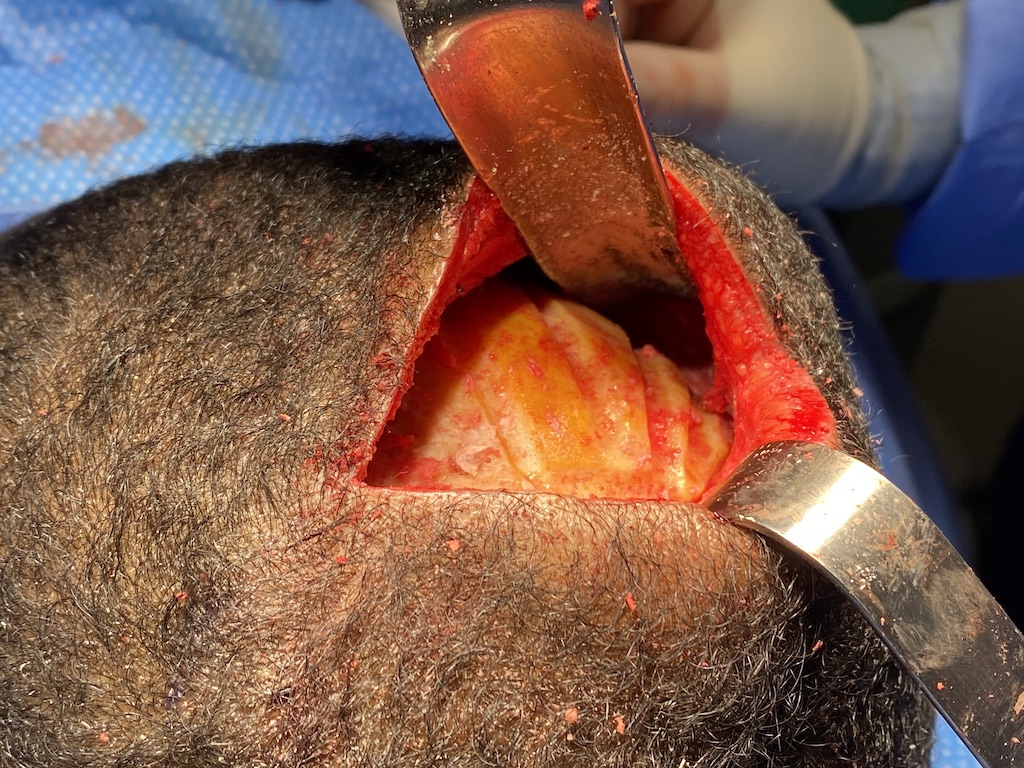

Desire to augment the flat upper back of his head. (crown augmentation)

Placement of custom skull implant through a small scalp incision to round out the flat upper back of his head.

Desire to augment the flat upper back of his head. (crown augmentation)

Placement of custom skull implant through a small scalp incision to round out the flat upper back of his head.